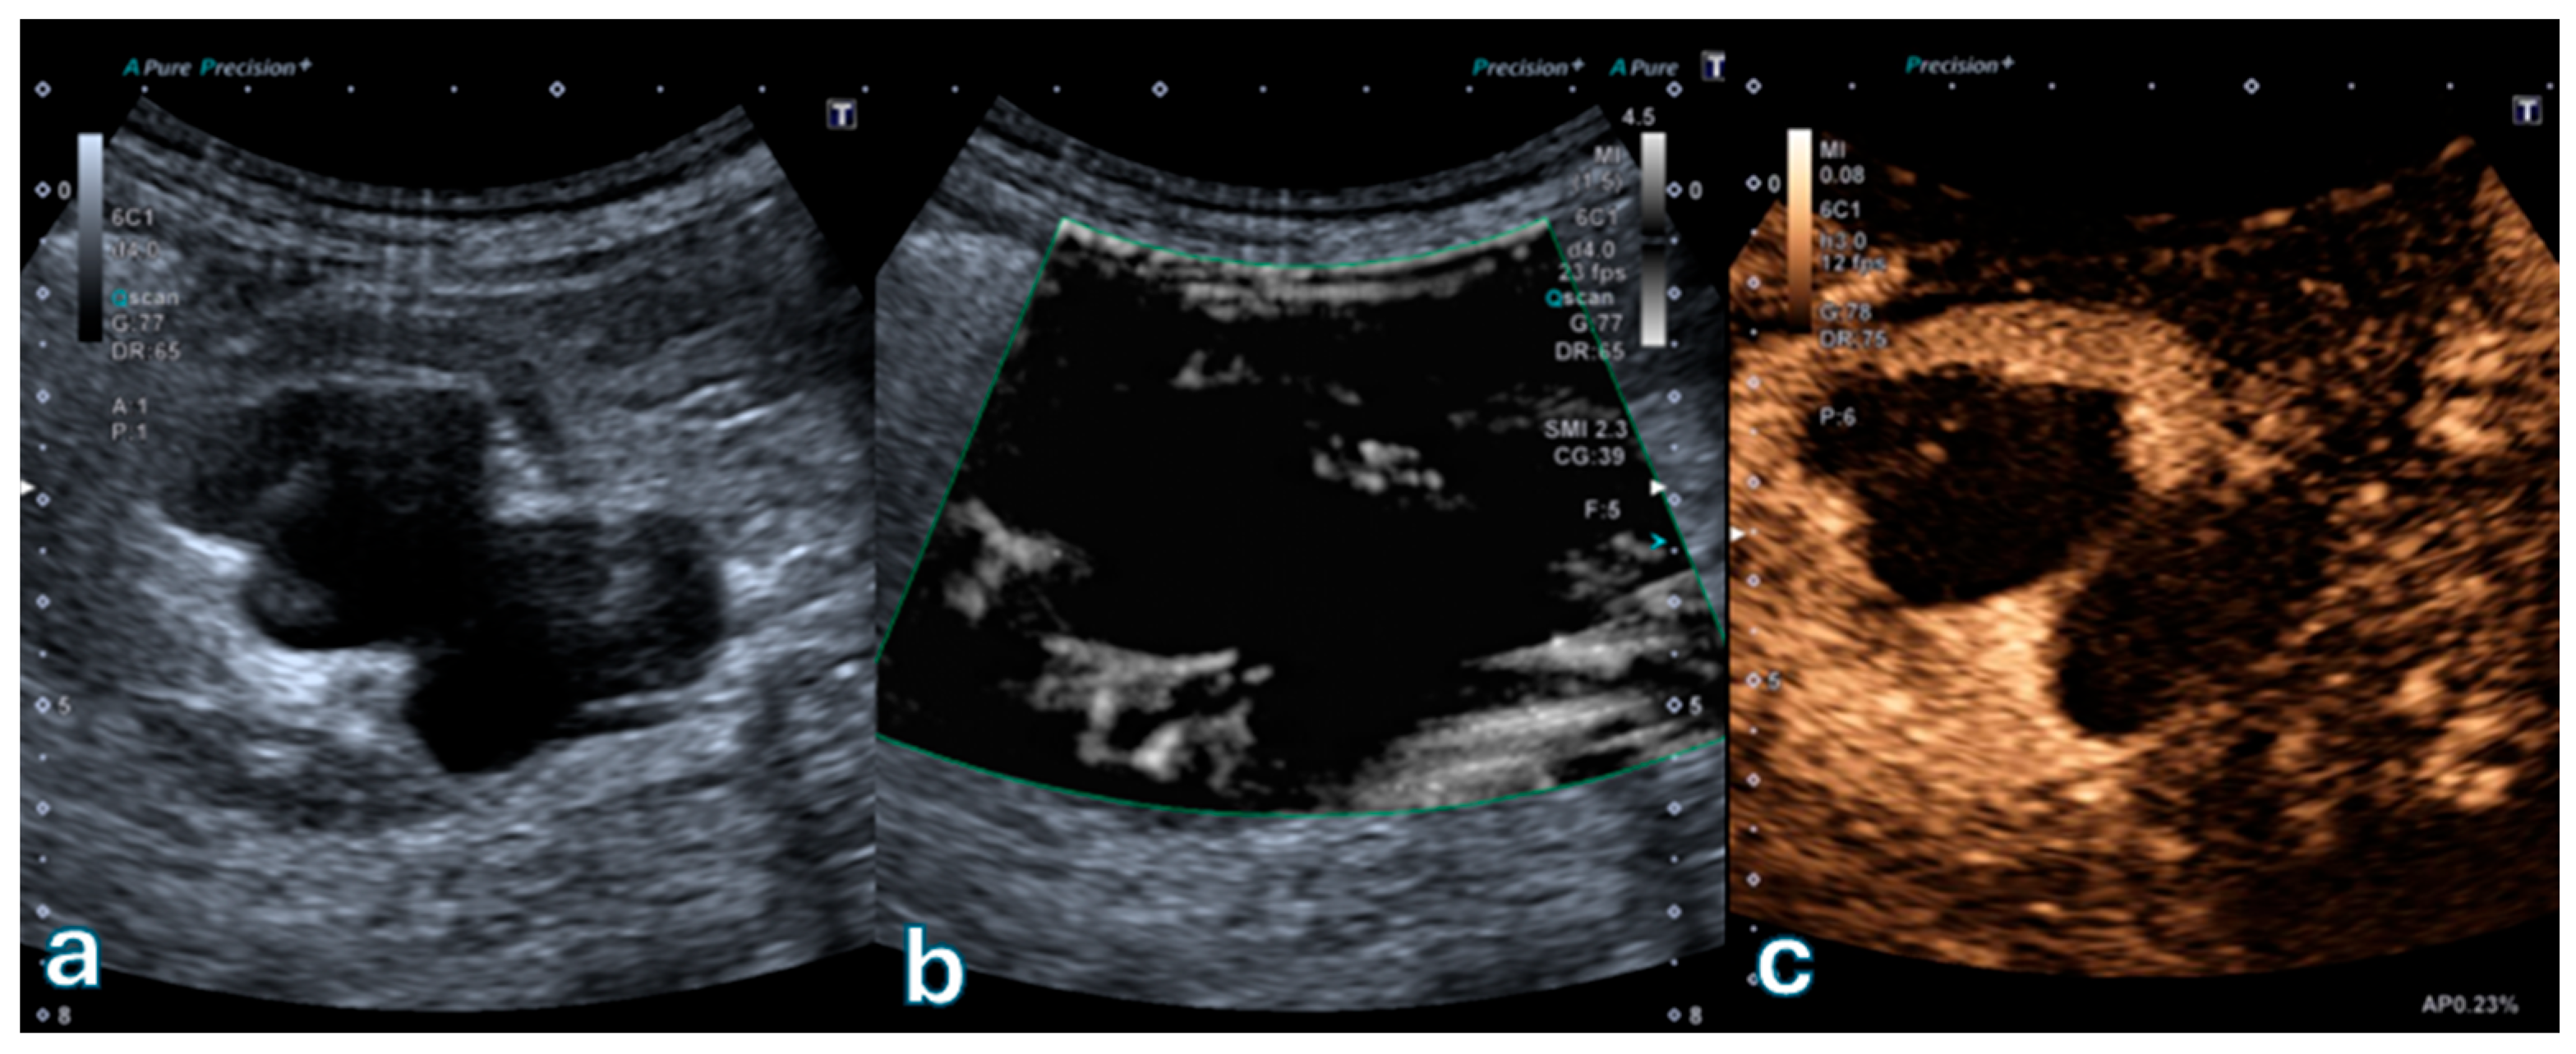

Figure 4 depicts a Bosniak IV cystic lesion characterized by a vascularized solid component visible on both SMI and CEUS, confirming their concordant diagnostic performance in detecting solid enhancing tissue.

Figure 4. Partially cystic renal lesion with an eccentrically located, heterogeneously hyperechoic solid component. (a) B-mode ultrasound shows a mixed cystic–solid lesion with irregular internal architecture. (b) Superb Microvascular Imaging (SMI) demonstrates distinct microvascular flow signals within the solid component, indicating true vascularity. (c) Corresponding contrast-enhanced ultrasound (CEUS) image confirms contrast enhancement of the same solid area, consistent with a Bosniak IV lesion according to the 2019 Bosniak classification. This case exemplifies complete concordance between SMI and CEUS in detecting vascularized mural components suggestive of malignancy.